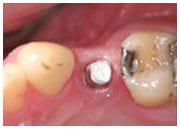

植牙過程

.jpg)

治療前

植入植體

治療後